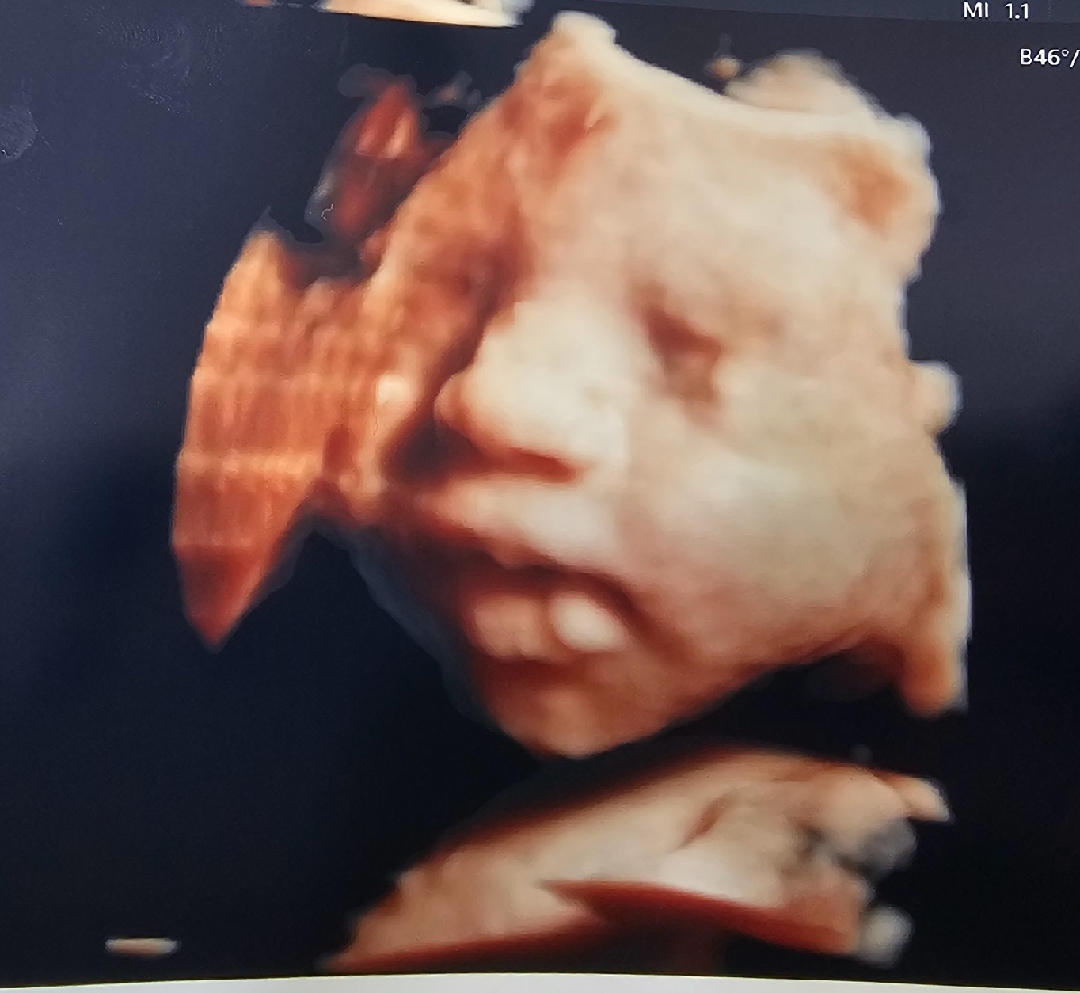

초음파 볼때마다 손으로 가려서 그동안 얼굴을 잘안보여줬는데 오늘 초코에몽 먹고 가서 그런지 너무 활발하게 움직여주고 손도 안가리고 눈코입도 잘보여주고 따봉도 날려줘서 너무 행복했어요♡ 남편 얼굴이 보이는 저도 닮은거같고 너무 신기해용